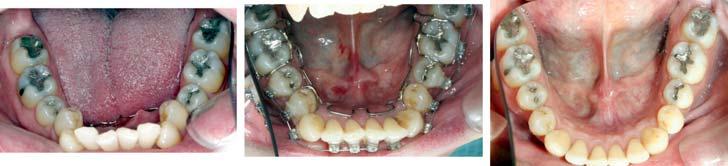

The ALF facilitates the remodeling of the maxilla and mandible to what might have been their genetically predetermined position. “During development, balance is continuously transient and can never actually be achieved because growth itself constantly creates ongoing normal regional imbalances.”12 The sources of imbalance in growth and development can be attributed to the brain, the basicranium, the airway, and growth of the oral region.13 Breathing, the infantile swallow, cranial distortions, oral habits, and all the other critical events that human beings go through can also interfere with normal growth and development. The patient in Figure 5 presented with evidence of all the above listed issues and was treated with ALF appliances, brackets, and wires.

The expansion in the premaxilla can be very substantial as shown in Figures 5 and 7. Reshaping of the mandible seems to occur within the alveolar bone.

Figure 9 demonstrates realignment of the teeth and distalization of the molars to create room for implants and CEREC® crowns.